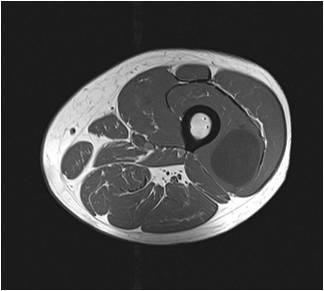

Gallery of Unlabled Radiographs from Lecture (Dr. French) - 2020

Click a thumbnail to enter the gallery display. Click the file name link at the bottom left of the gallery display to view the image at high resolution.